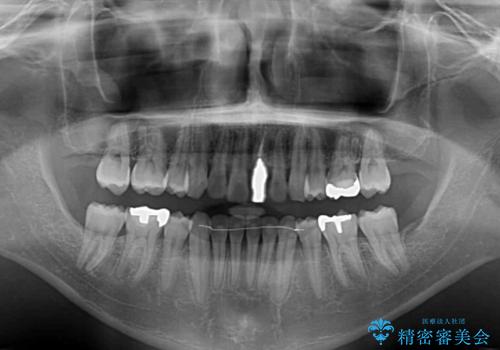

- 下顎の八重歯を気にして来院された患者様です。

左下以外、3本の第一小臼歯が既に抜去されており、左下は八重歯になっている状態でした。

左下の八重歯は手前に傾斜していたため、インビザラインによる抜歯矯正が可能と判断し、後方にある第一小臼歯を抜歯してインビザラインにて矯正治療を行うこととしました。